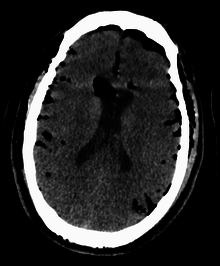

CT scans of patients with a tension pneumocephalus typically show air that compresses the frontal lobes of the brain, which results in a tented appearance of the brain in the skull known as the Mount Fuji sign.[1][2][3] The name is derived from the resemblance of the brain to Mount Fuji in Japan, a volcano known for its symmetrical cone. In typical cases, there is a symmetrical depression near the midline (such as the crater of a volcano), due to intact bridging veins.[3] Its occurrence seems to be limited to tension pneumocephalus (not occurring in pneumocephalus without tension).[4] The sign was first described by a team of Japanese neurosurgeons.[5]